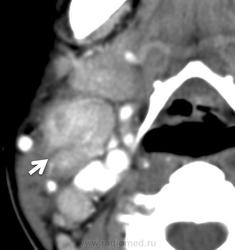

Кикучи синдром (Кикучи – Фуимото болезнь, описана японскими врачами M. Kikuchi, Y. Fujimoto; синоним – гистиоцитарный некротизирующий лимфаденит) – заболевание, проявляющееся безболезненным односторонним поражением шейных лимфатических узлов с возможной последующей генерализацией лимфаденопатии, лихорадкой, поражением кожи по типу крапивницы, иногда – спленомегалией. Увеличение мезентериальных лимфоузлов может симулировать аппендицит. При лабораторном обследовании выявляют нейтропению, лимфоцитоз, ускорение СОЭ, увеличение концентрации печеночных ферментов, в сыворотке крови обнаруживают антитела к ДНК, антилимфоцитарные антитела. При гистологическом исследовании лимфоузлов – пятнистый паракортикальный некроз из эозинофильного материала, окруженный гистиоцитами, макрофагами, Т-клетками. Предполагается, что волчанкоподобный синдром развивается в связи с инфекцией, вызванной парвовирусом. Терапия – глюкокортикоиды.